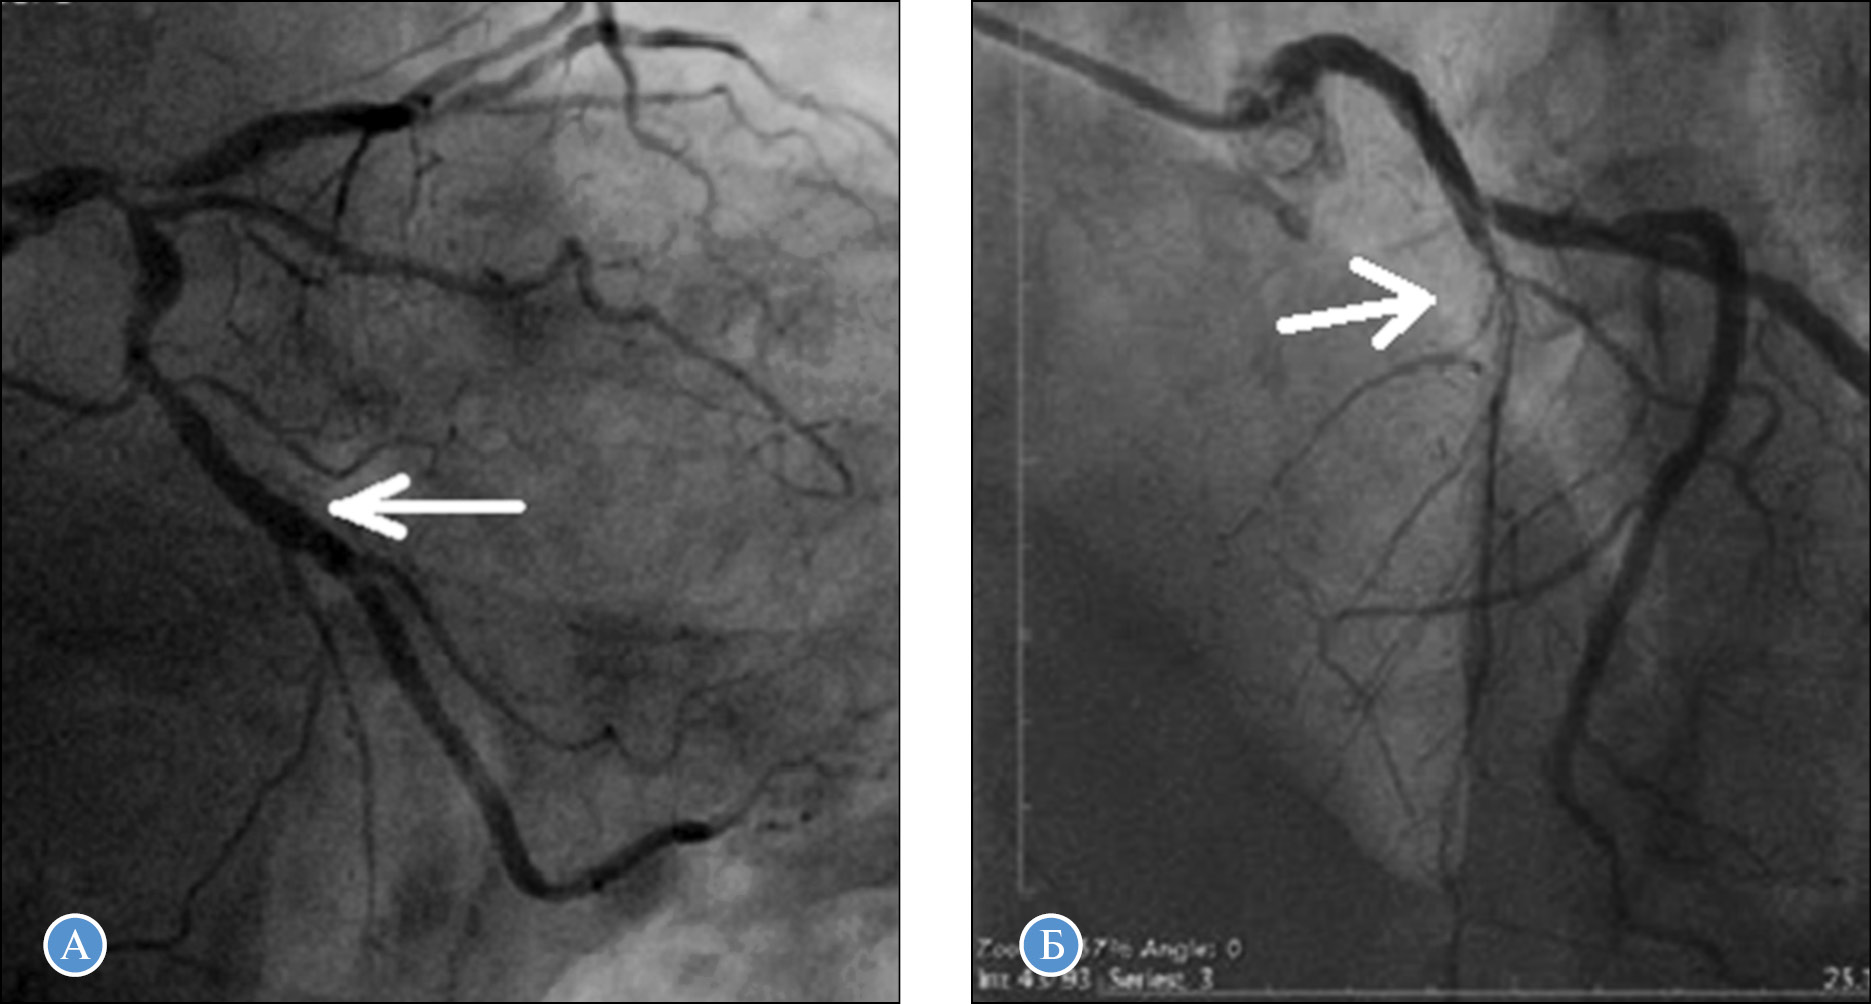

Критерии соответствия

Рис. 1. Примеры расчета индекса диффузного поражения (ИПД): А — артерия тупого края является доминантной (0 баллов) в бассейне ОА, нет признаков коронароатеросклероза дистальнее стеноза (0 баллов) и диаметр сосуда более 2 мм (0 баллов), поэтому ИДП равен нулю; Б — передняя нисходящая артерия, у которой ИДП равен 9, диаметр артерии — менее 1 мм (3 балла), стенозирующий атеросклероз на всем протяжении (3 балла), сосуд является редуцированным (3 балла)